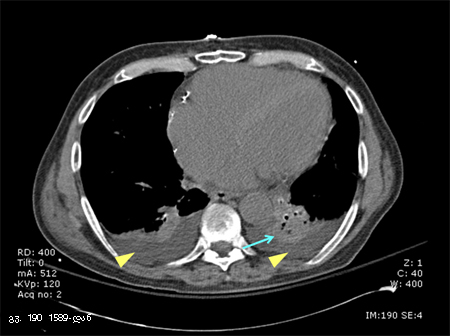

პაციენტის კომპიუტერული ტომოგრაფია, რომელსაც აქვს მარცხენა ქვედა წილის ალვეოლური ინფილტრაცია (ლურჯი ისარი), ორმხრივი პლევრალური ექსუდატი (ყვითელი ისრის წვეტები) და მარჯვენა ბაზილარული ატელექტაზი; ყურადღება მიაქციეთ ხაზს, რომელიც მიჯნავს ნაცრისფრის ორ ტონს, რომელთაგან ერთი წარმოადგენს ინფილტრაციას და მეორე სითხეს.